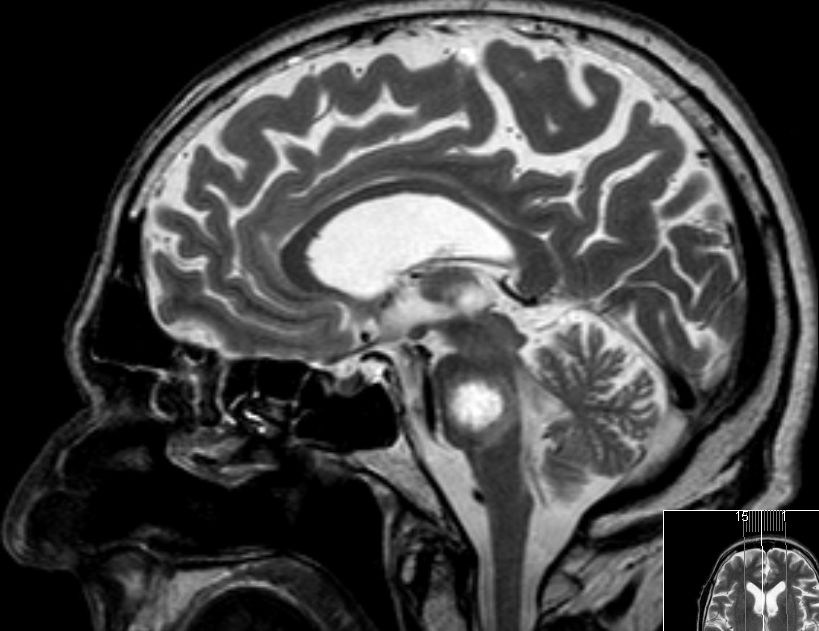

| MRT: multiple Hirnmetastasen | Adenokarzinom der Lunge. MRT-Untersuchung des Hirns. | |||